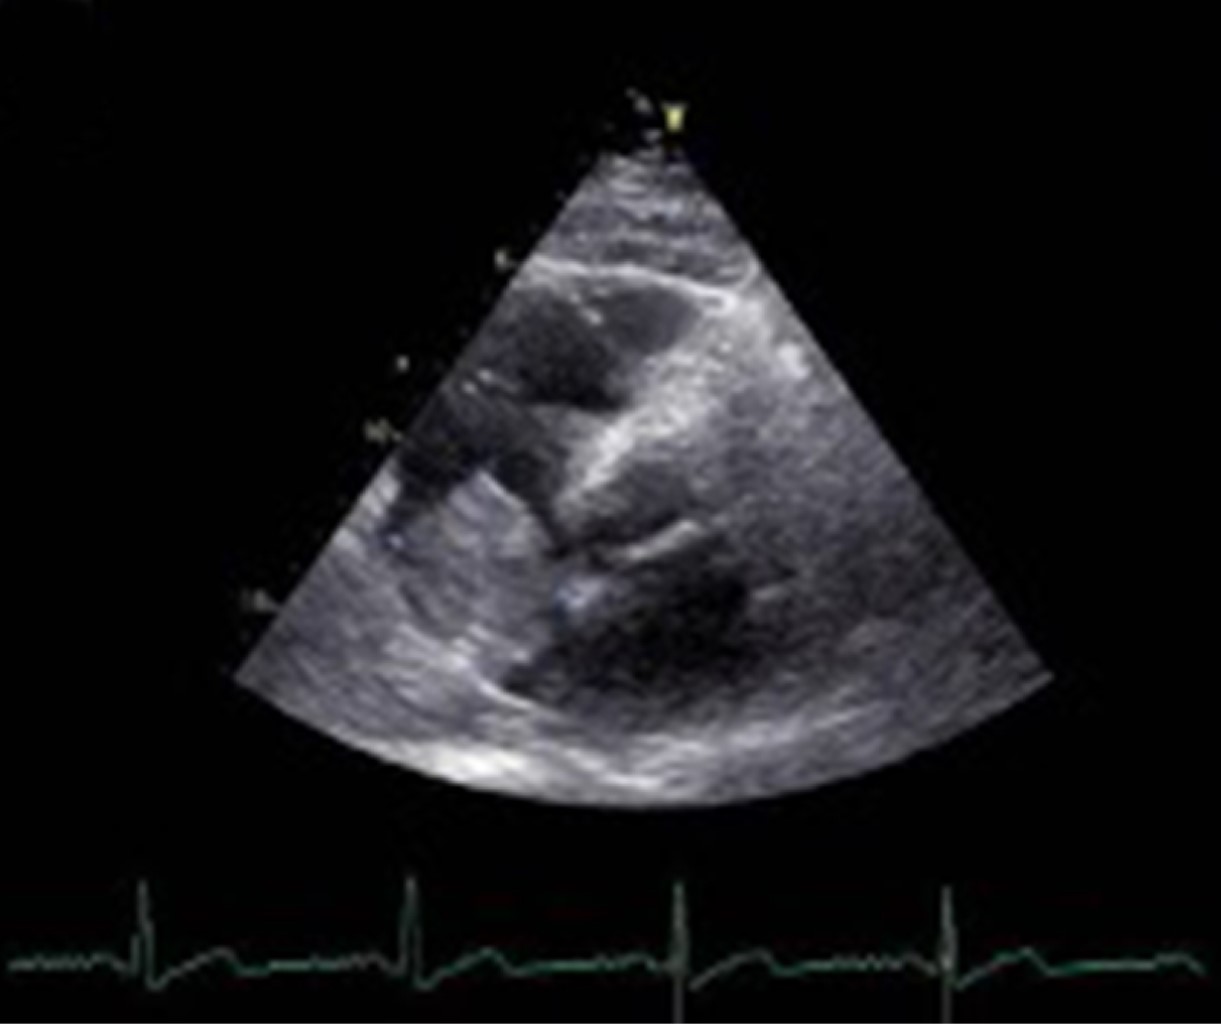

Mixoma cardiaco auricular derecho, dos presentaciones diferentes de una misma entidad y hallazgos histopatológicos

Introducción: los mixomas cardiacos son las neoplasias primarias más frecuentes del corazón. La ubicación más común es la aurícula izquierda (75%), seguido de la aurícula derecha (15-18%) y ventrículo izquierdo. Pueden presentarse con la tríada de síntomas obstructivos, embólicos y constitucionales. Caso 1: varón de 59 años en seguimiento por linfoma cutáneo no Hodgkin de linfocitos T, que padecía disnea progresiva y presentaba una masa localizada en la aurícula derecha. Se realizó resección del tumor y reemplazo de la válvula mitral debido a insuficiencia mitral severa. La histopatología confirmó el diagnóstico de mixoma. Caso 2: mujer de 61 años que consulta por trombosis en vena basílica, cefálica y yugular derecha. Un ecocardiograma mostró una masa cardiaca de 80 × 40 mm en la aurícula derecha. En el informe histopatológico se informó un mixoma cardiaco con el diámetro mayor de 7.5 cm. Fue dada de alta nueve días después de la cirugía. Conclusión: podría haber una presentación inusual de mixoma auricular que ocurra simultáneamente con una neoplasia de diferente linaje. Debe sospecharse mixoma auricular, incluso en ubicaciones inusuales e independientemente de la enfermedad neoplásica concomitante. Los fenómenos embólicos, como la primera presentación, pueden inducir a error; aunque algunos parámetros y puntuaciones pueden ser predictores útiles.

Figura 1

Figura 2

Figura 3

Figura 4

Figura 5

Figura 6

Figura 7

Figura 8